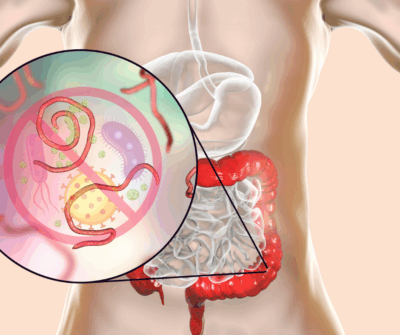

Parasites are organisms that live on or inside another living being (the host) and obtain nutrients from that host. This relationship is a form of symbiosis where the parasite depends on the host for survival. Parasites can include certain plants, animals, insects, crustaceans, bacteria, and various types of worms.

After entering, the parasites develop from larvae into adults in the intestines, where they may begin to cause symptoms.